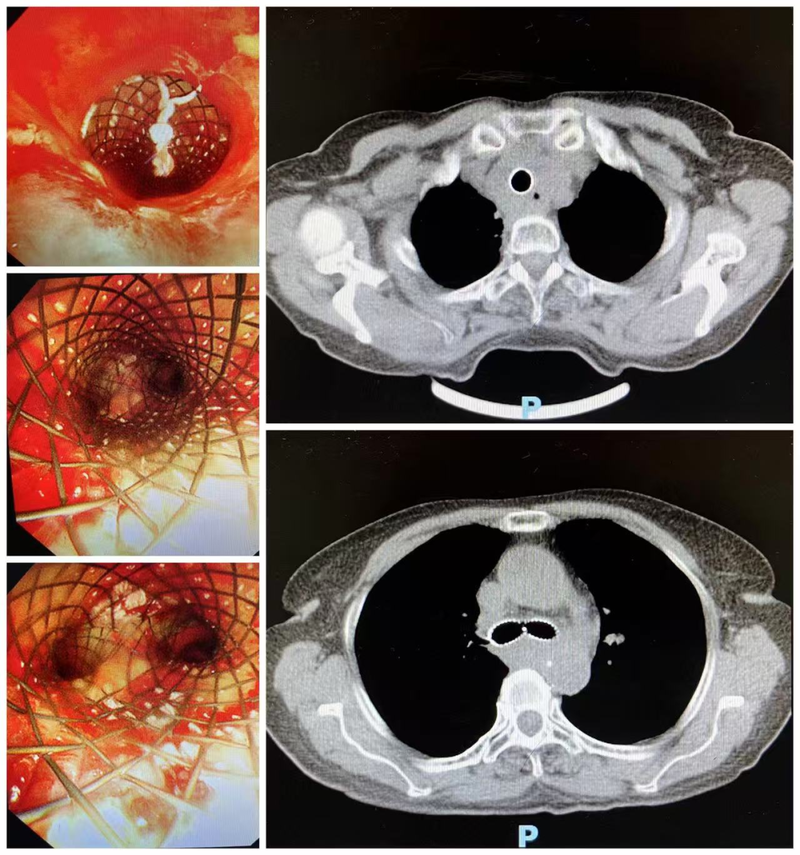

术前胸部CT及气管镜检查提示,患者大气道明显狭窄,狭窄处直径仅约6mm,长度约40mm,远低于正常人15–20mm的气管直径。此外,患者无法耐受缺氧,麻醉风险极高,手术难度大。面对这一复杂病情,肺病二科联合麻醉、医务部、内镜中心及重症医学科等多学科团队,全面评估患者情况,反复讨论并制定了周密的手术方案,全力保障患者安全。

9月12日,在多学科密切配合下,患者在全麻状态下成功接受了硬质气管镜下Y型金属覆膜支架置入术,撑开了被肿瘤挤压的“生命要道”。术后,患者呼吸困难症状显著改善,当日转入重症监护室观察,次日病情稳定转回普通病房。复查影像及气管镜显示,气管管腔通畅,支架位置理想、扩张良好,未见明显并发症。患者术后恢复顺利,5天后康复出院。

患者术后胸部CT及镜下图片